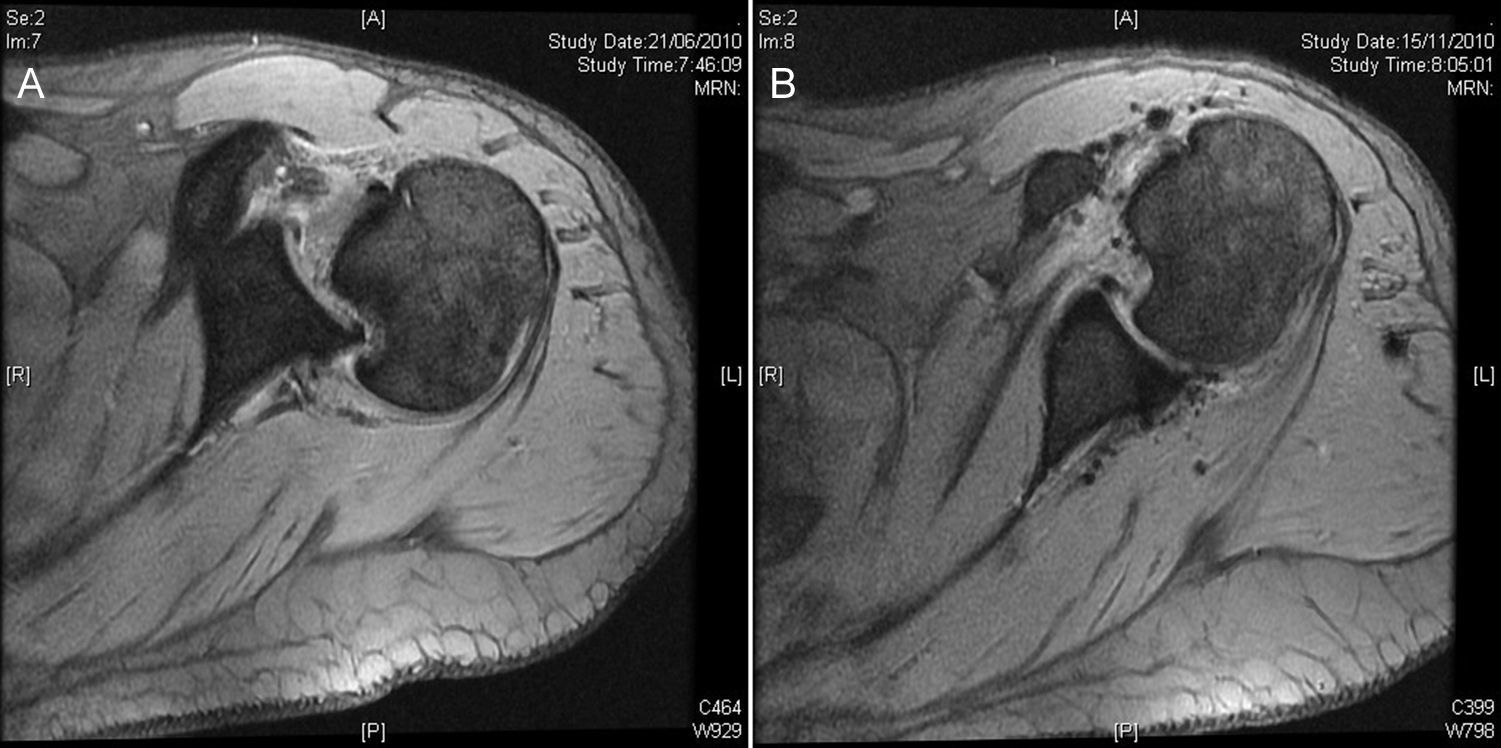

Fue trasladado al hospital más próximo y valorado por un médico de urgencias; se le realizaron radiografías que se consideraron normales y se diagnosticó una contusión de hombro y se remitió a su médico de atención primaria para control de la evolución. Tras 6 semanas el paciente no evolucionaba bien y se remite a consultas externas de traumatología. El paciente presentaba dolor y gran limitación funcional, con una flexión de 80°, abducción de 70° y 0° de rotación externa, con artrofia del deltoides y del infraespinoso y con actitud antiálgica en rotación interna. En la radiografía simple se diagnosticó una luxación posterior de hombro y se solicitó una RMN urgente, que mostraba una luxación posterior bloqueada del hombro derecho con un defecto óseo anterior en la cabeza humeral y una lesión del labrum posterior (fig. 1A). El paciente se intervino a los 2 días de la visita en consultas externas de traumatología.

Caso 1, hombro derecho. A. Imagen de la resonancia magnética preoperatoria donde podemos ver la luxación posterior del hombro bloqueado, la lesión de Hill Sachs inversa y la lesión de Bankart inversa. B. Imagen de la RM después de 5 meses de la cirugía artroscópica. Podemos ver el tendón subescapular llenando el defecto de hueso de la cabeza del húmero, el labrum posterior cicatrizado y la cabeza humeral centrada en la cavidad glenoidea.

En la RMN de control a los 5 meses se puede apreciar la cabeza humeral centrada en la glena, el mantenimiento del espacio glenohumeral y el subescapular rellenando el defecto óseo (fig. 1B).